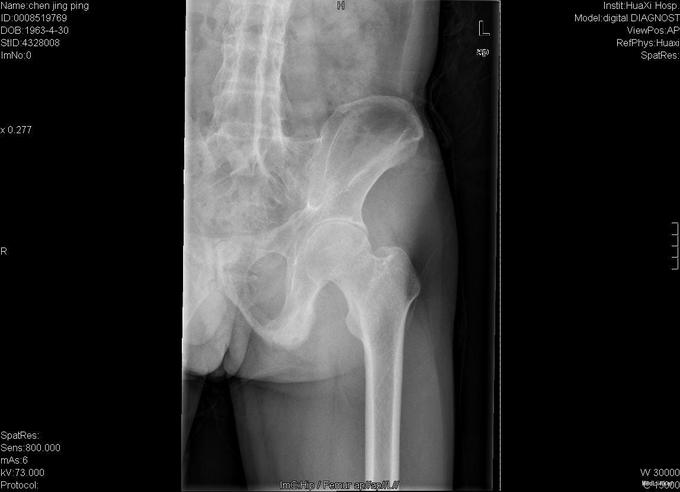

查体:跛行步态,强迫体位,脊柱强直后凸畸形,活动受限。右髋强直畸形,压痛、叩痛,无瘢痕、窦道,无皮损、皮癣,活动受限。双下肢感觉无明显异常。 辅助检查:x线片:脊柱呈"竹节样"改变,腰椎小关节间隙模糊,双侧骶髂关节及右髋关节间隙消失,骨性融合。

诊断:强直性脊柱炎 右髋关节强直 治疗:完善相关检查后在全麻下行右侧全髋关节置换术+髋臼成形术,手术顺利,术后予以抗炎+抗凝+阵痛等治疗。